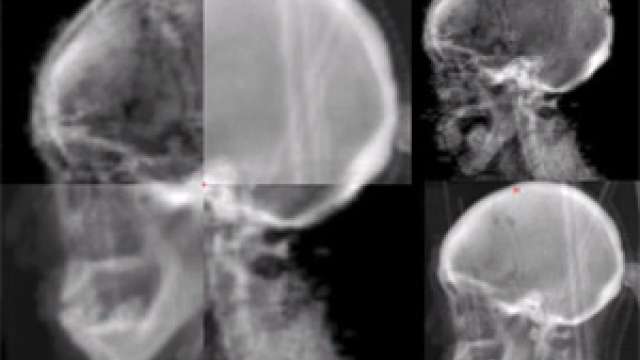

Acoustic Neuroma

Acoustic neuroma is a rare noncancerous tumor. It grows slowly from an overproduction of Schwann cells and is also called a vestibular schwannoma.